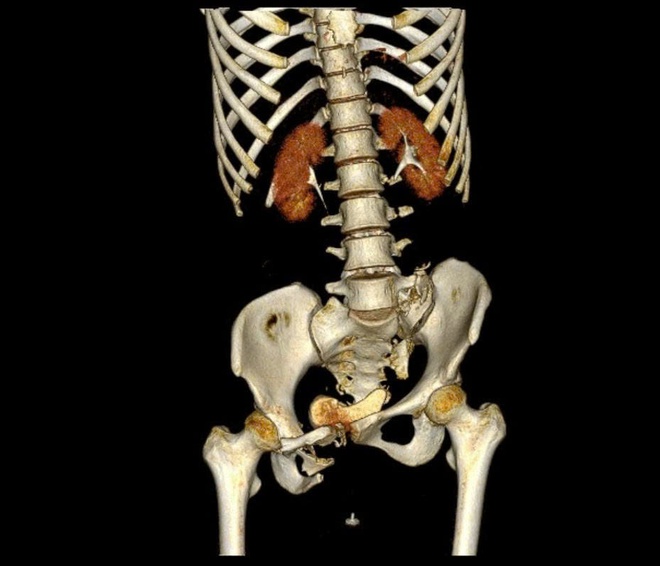

Bệnh nhân gãy khung chậu phức tạp, đa chấn thương và sốc chấn thương nặng do tai nạn giao thông. Ảnh: BVCC.

BS.CKI Trần Quang Khanh - Khoa Phẫu thuật chi dưới, Viện Chấn thương Chỉnh hình, Bệnh viện Quân y 175 cho biết: "Bệnh nhân bị gãy khung chậu kiểu 'gió thổi' (Windswept pelvic ring fracture) – một dạng gãy rất phức tạp, chiếm khoảng 6% các trường hợp gãy khung chậu. Đây là loại gãy do chấn thương năng lượng cao, kết hợp giữa lực nén trước - sau và lực tác động bên, khiến một bên cánh chậu mở ra, bên còn lại khép lại, tạo hình ảnh đặc trưng như 'bị gió thổi'. Thường tổn thương còn đi kèm gãy xương cùng và tổn thương khớp mu, làm mất vững toàn bộ vòng chậu, gây nguy hiểm tính mạng nếu không được xử trí đúng cách".

Khung xương chậu bệnh nhân trước và sau phẫu thuật. Ảnh: BVCC.